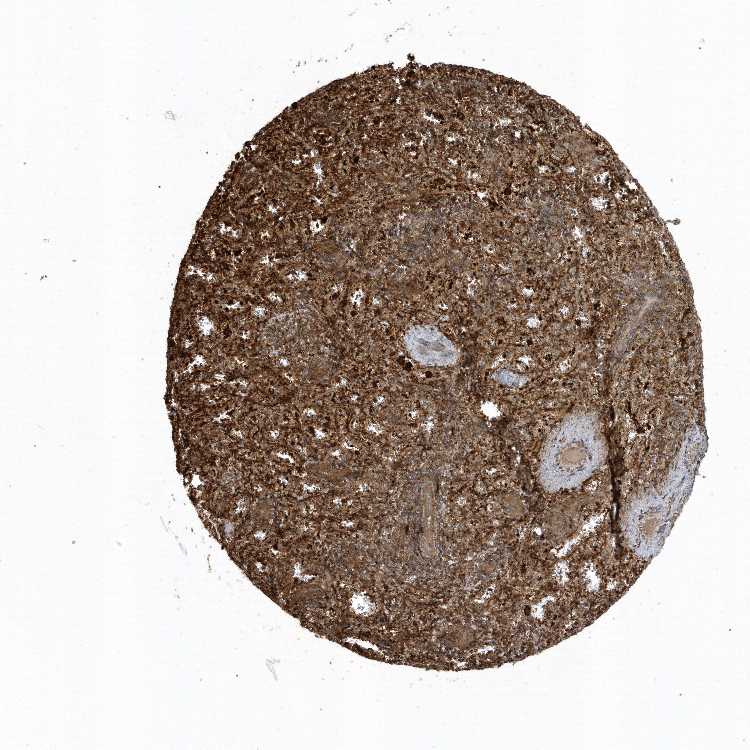

SPLEEN - Antibody stainingi

Antibody staining in the annotated cell types in the current human tissue is reported as not detected, low, medium, or high, based on conventional immunohistochemistry profiling in selected tissues. This score is based on the combination of the staining intensity and fraction of stained cells.

Each image is clickable and will lead to virtual microscopy that enables deeper exploration of all samples and also displays staining intensity scores, fraction scores and subcellular localization as well as patient and tissue information for each sample.

Antibody HPA035480Antibody HPA035481

Cells in red pulp HighNot detected

Cells in white pulp MediumNot detected